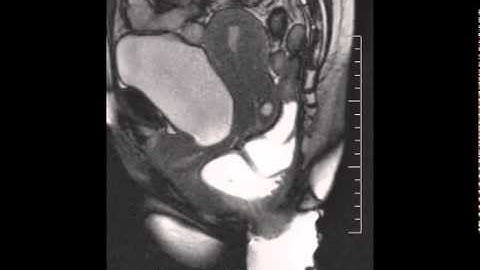

Intussusception Video